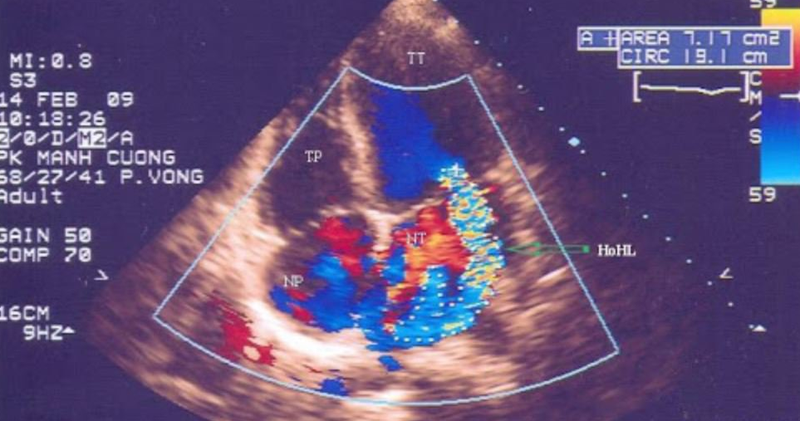

Siêu âm Doppler tim là một trong những phương pháp chẩn đoán hình ảnh được sử dụng phổ biến hiện nay. Đây là kỹ thuật không xâm lấn giúp kiểm tra, đánh giá các dấu hiệu bất thường và chẩn đoán các bệnh lý về tim mạch. Vậy phương pháp này có ưu điểm gì và quy trình siêu âm ra sao?

Kỹ thuật siêu âm Doppler tim được sử dụng trong chuyên khoa tim mạch với mục đích chính là quan sát chuyển động của tim, kiểm tra chức năng của các van tim, cơ tim, chẩn đoán và theo dõi hiệu quả các bệnh lý về tim mạch. Quy trình siêu âm Doppler tim có thể được thực hiện tại phòng siêu âm chuyên dụng ở bệnh viện hoặc siêu âm cấp cứu tại giường bệnh.

Nhiều người bệnh cảm thấy lạ khi nghe bác sĩ chỉ định thực hiện siêu âm Doppler tim. Vậy siêu âm Doppler tim là gì? Phương pháp này được dùng để thăm dò, chẩn đoán hình ảnh nhằm đánh giá cấu trúc, trạng thái hoạt động của tim, trạng thái huyết động hay tình trạng chuyển dịch của máu trong hệ tuần hoàn. Từ đó, phát hiện các dấu hiệu bất thường hoặc các bệnh lý tại hệ thống tim mạch. Nhờ công dụng trên, siêu âm Doppler tim thường được các bác sĩ chỉ định và sử dụng nhiều trong việc chẩn đoán và đánh giá bệnh tim mạch.

Đầu dò có thể điều chỉnh được để có các góc nhìn khác nhau và trực tiếp đánh giá các thông số trên hình ảnh siêu âm. Bác sĩ có thể thu lại các hình ảnh bất thường để hội chẩn với các chuyên gia về tim mạch nhằm đánh giá các bất thường của cơ tim và các van tim, chức năng tống máu của tim,... Kết hợp quan sát điện tâm đồ cùng với hình ảnh siêu âm Doppler tim để quan sát được dòng máu đang ở thì tâm trương hay tâm thu hay ở cả hai thì.